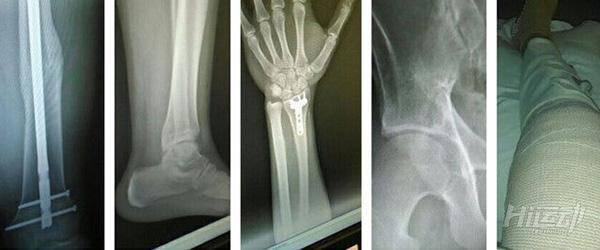

這場車禍將他撞了近20米遠,導致了他雙腿骨折,左大腿被刺穿,腳踝骨折,骨盆骨折,肩胛錯位,手腕骨折,腎臟錯位,膀胱破裂,脊椎開裂。

從頭到腳都綁滿的繃帶,他的母親在身邊,住在另外一個州的姐姐也回了,他意識到這場車禍的嚴重性,也意識到,這就是現實。